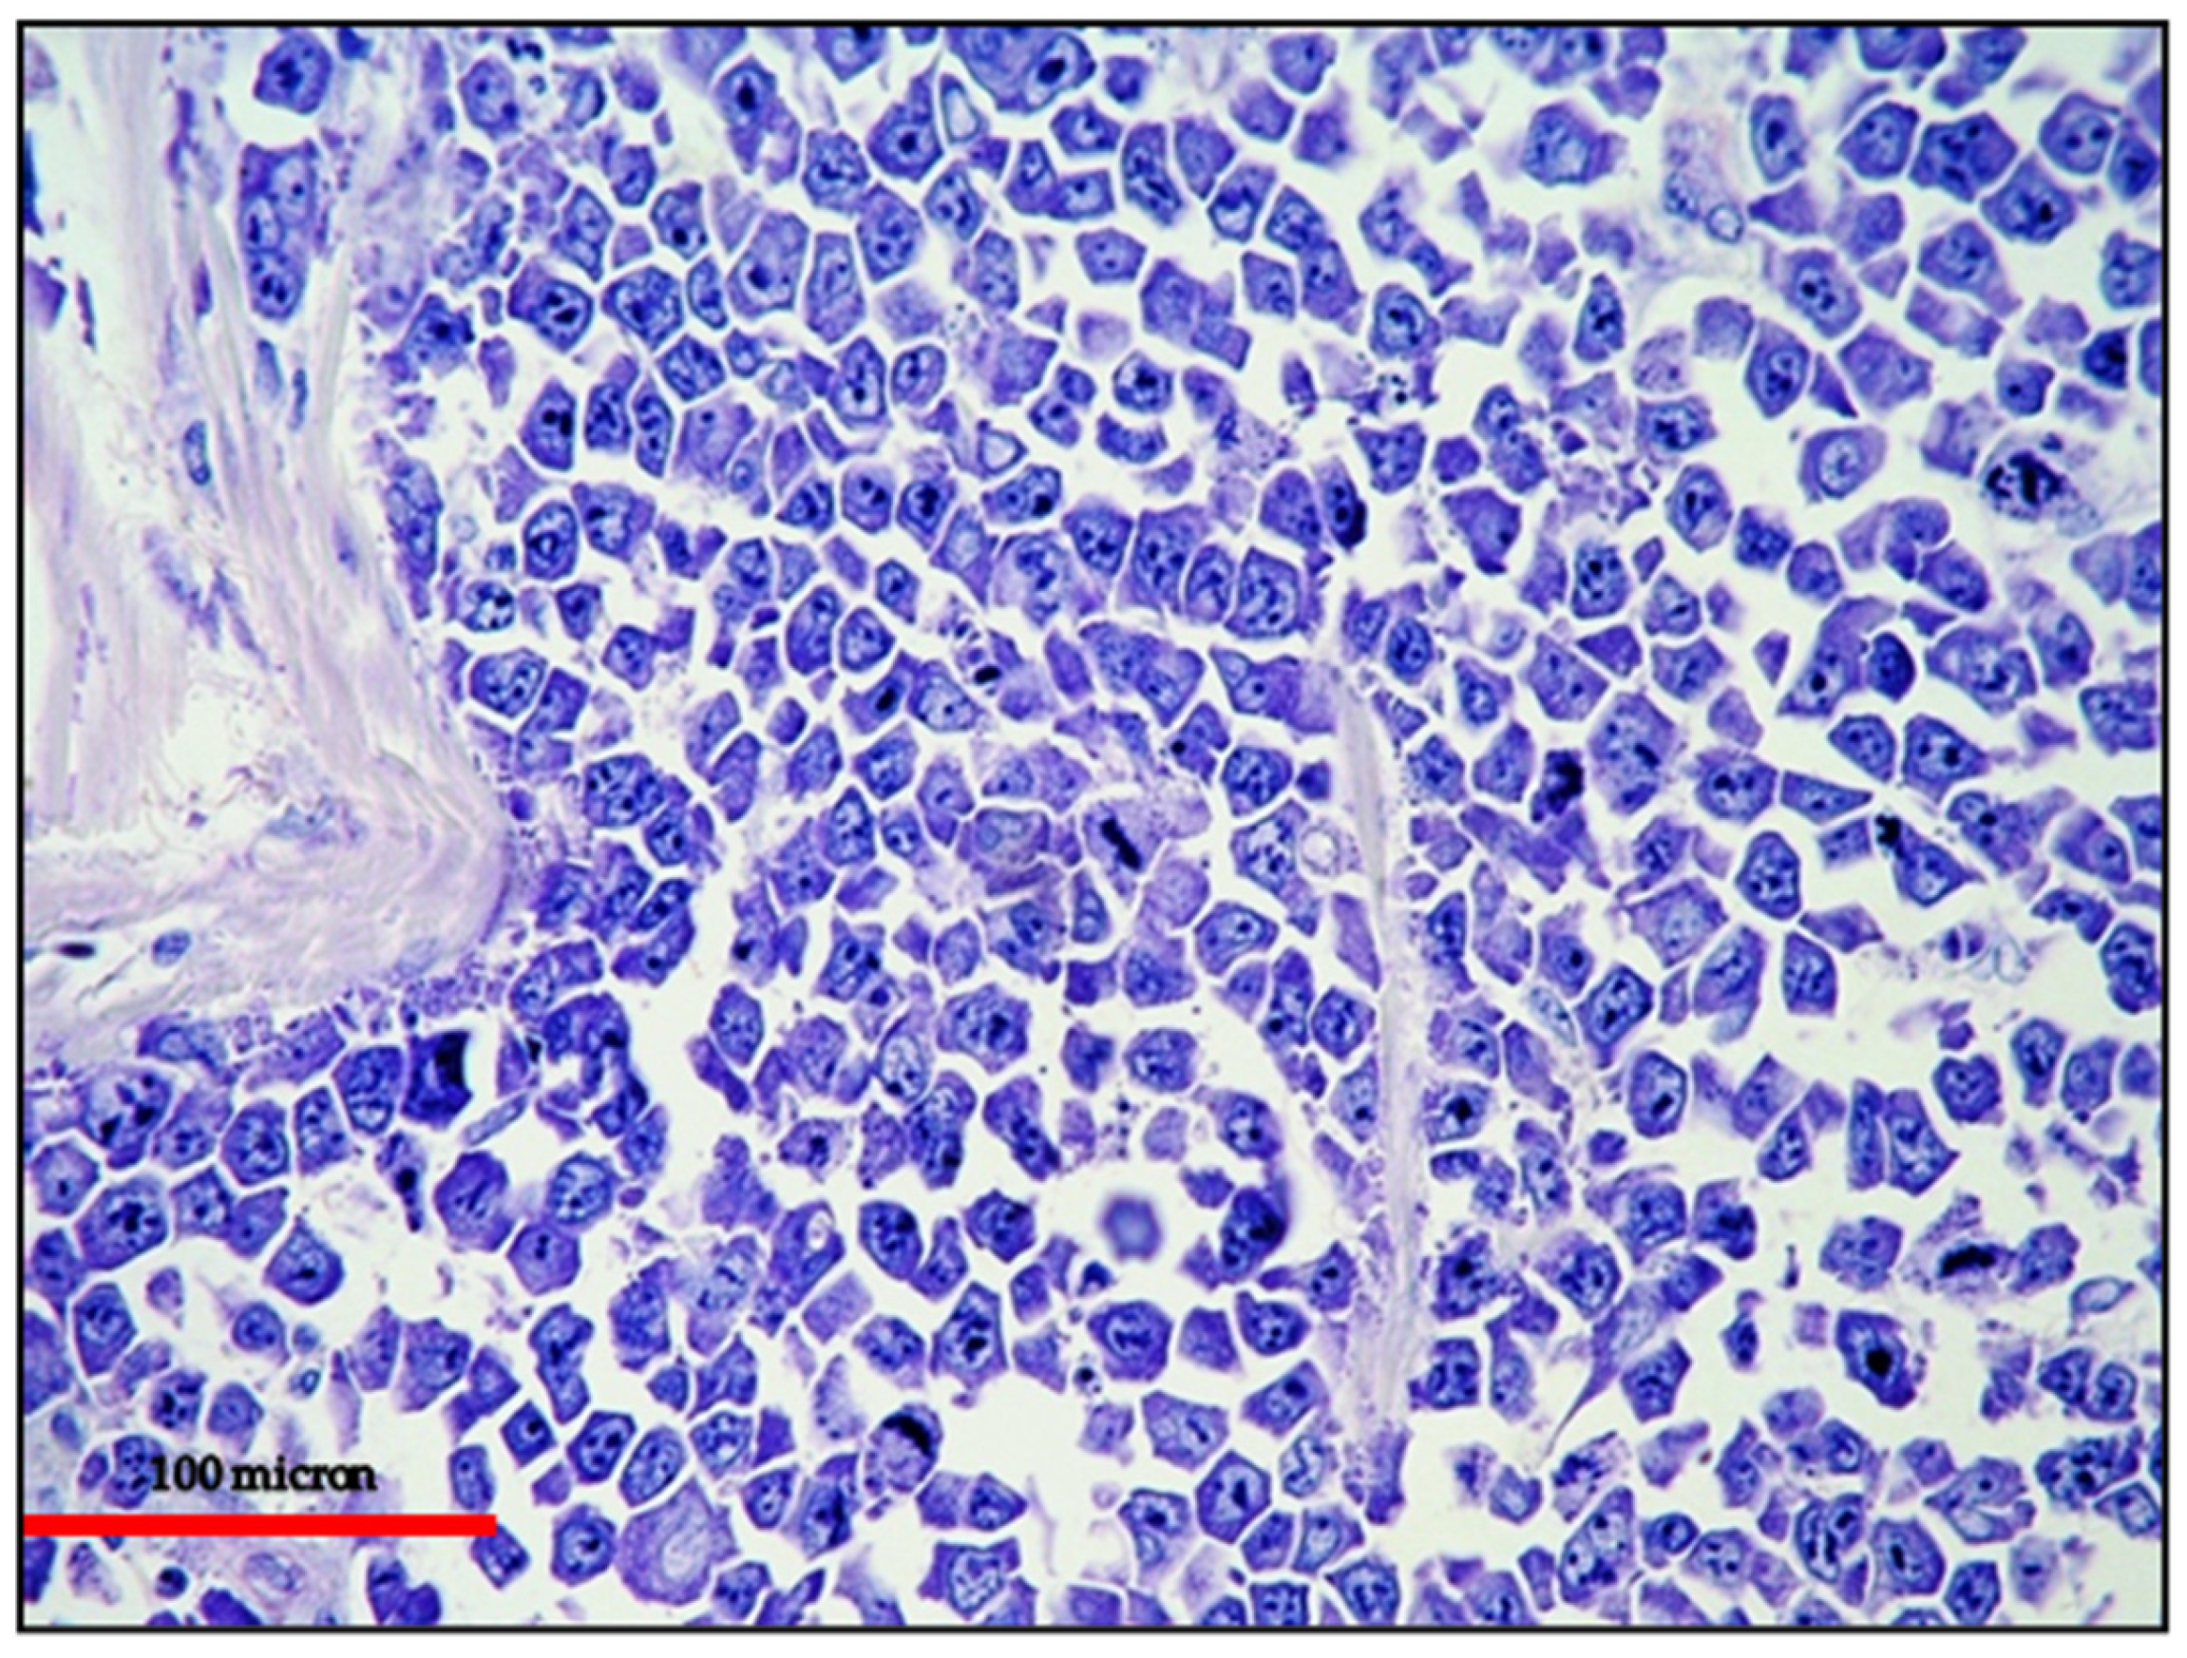

PEL in its classic form usually fails to express pan-B-cell markers such as CD19, CD20, CD79α and PAX5 as well as surface and cytoplasmic immunoglobulin. The classic form usually expresses CD45/LCA.

The extra-cavitary variant may express B-cell markers (25% vs. <5%), although not in all cases (Figure 6), as well as immunoglobulin (25% vs. 15%) more often than classic PEL and, on the other hand, may have a lower expression of CD45 [70].

Figure 6.

EC-PEL of the ileum: in this case, the neoplastic proliferation lacks B-cell marker expression; this is often a common feature of neoplasms with plasma cell differentiation such as PBL and PEL (CD20 immunostaining, Ventana immunostainer, magnification 200×; original image from Prof Ascani).